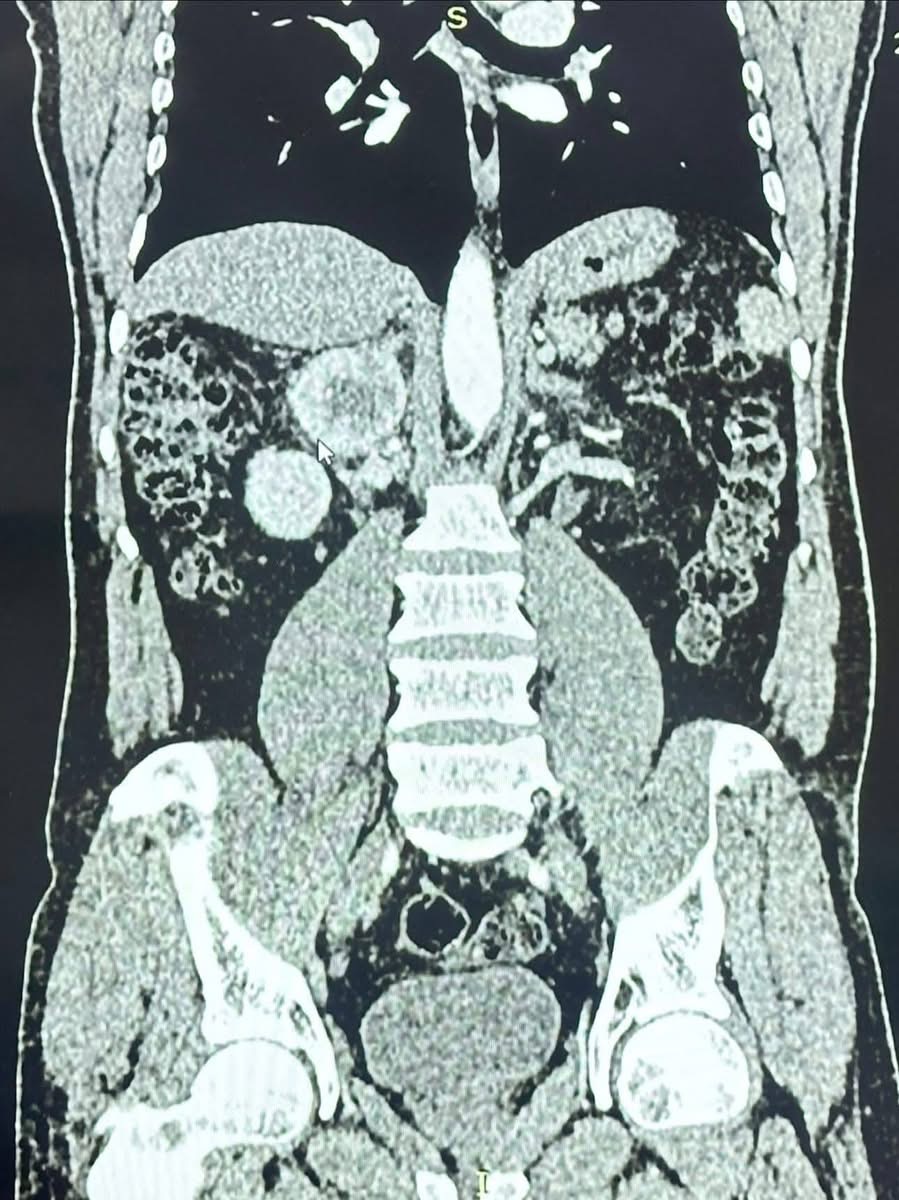

المريض، البالغ من العمر ٤٤ عامًا، راجعَ مركز الفيحاء التخصصي بعد معاناة طويلة من ارتفاع شديد في ضغط الدم وتسارع حاد في ضربات القلب. وبعد إجراء الفحوصات اللازمة، تبيّن وجود ورم كبير في الغدة الكظرية اليمنى، يفرز كميات مرتفعة جدًا من هرمون النور أدرينالين (Pheochromocytoma)، ما شكّل خطرًا كبيرًا على حياته.